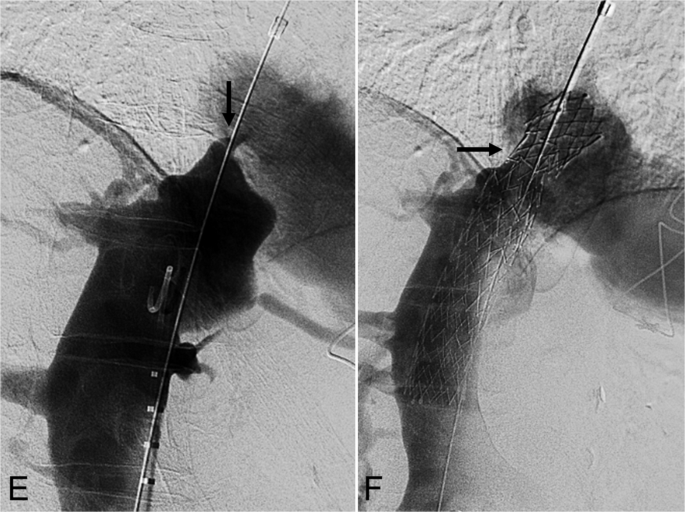

一名76岁的男性,在因非扩张型缺血性心肌病(ICM)接受OHT手术后4,756天,出现肝硬化、门脉高压和活动性呼吸困难。此次移植手术需要使用20毫米的Dacron移植物来延长腔静脉-心房吻合口。7天前的心脏导管检查显示初始压力差为11毫米汞柱。下腔静脉造影显示狭窄程度超过95%(图3E)。放置了一枚20毫米×120毫米的Abre支架,并扩张至16毫米。术后造影显示血流顺畅。IVUS和锥形束CT确认支架扩张效果良好(图3F)。最终腔静脉-心房压力差为2毫米汞柱。患者术后偶尔出现心悸,心电图显示窦性心律正常。随访影像显示支架位置稳定,症状在6天内消失。

一名76岁的男性,在因非扩张型缺血性心肌病接受OHT手术后4,756天,出现肝硬化、门脉高压和活动性呼吸困难。E 下腔静脉造影显示吻合口狭窄(黑色箭头)。F 重建后的造影显示20毫米×120毫米的Abre支架(黑色箭头)已放置到位,狭窄得到缓解